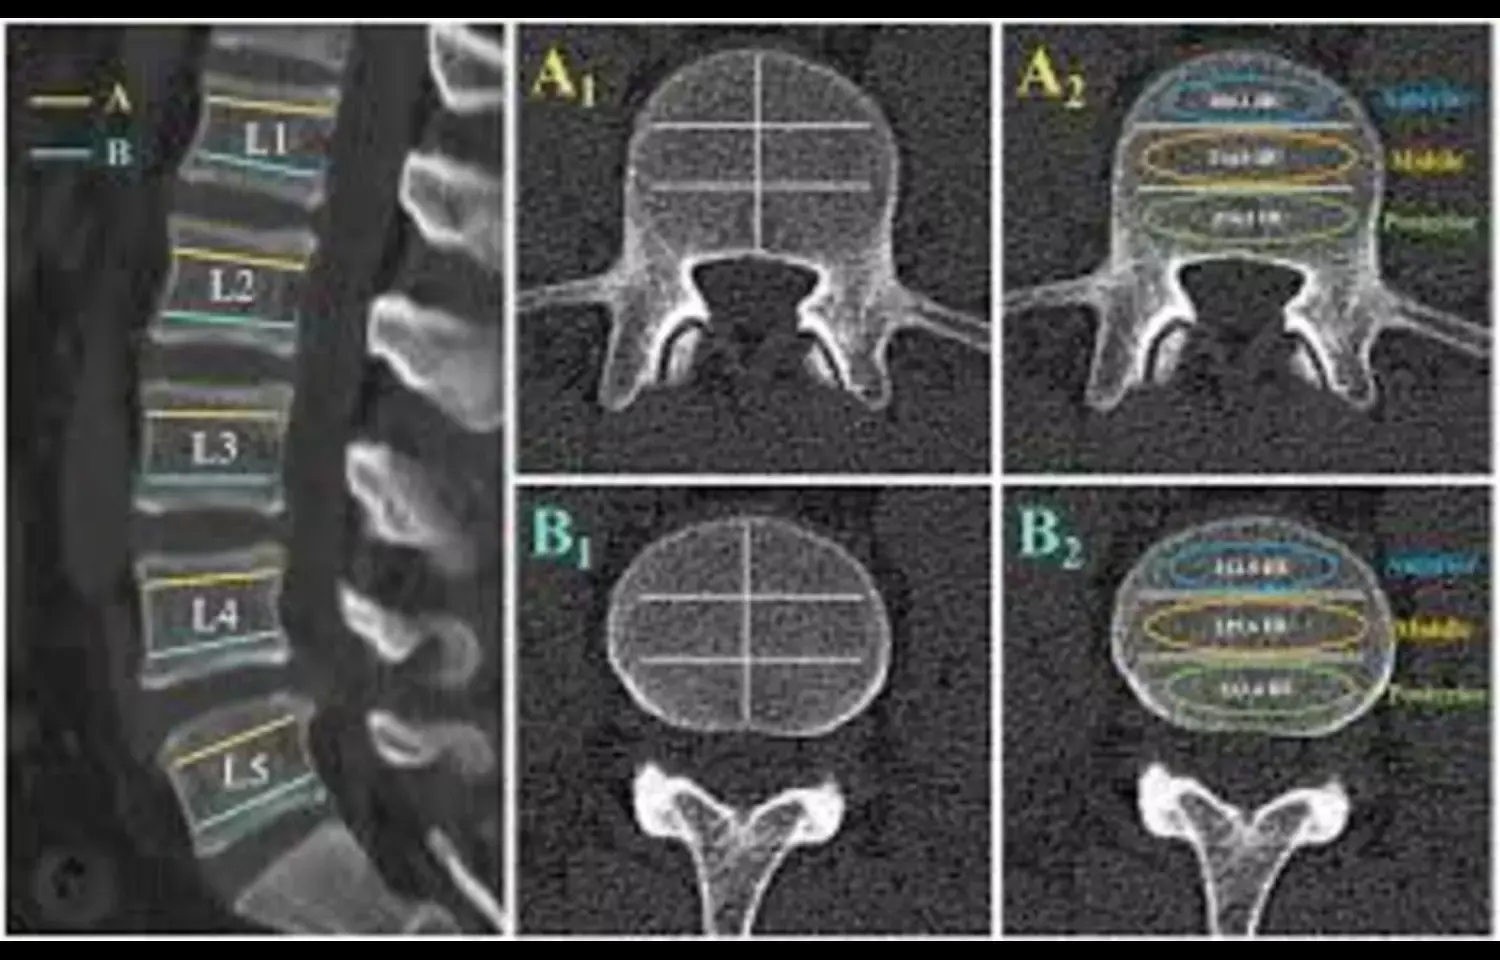

The relationship between insulin resistance (IR) and bone density is quite complex. The triglyceride glucose (TyG) index, which combines the assessment of glycolipid metabolism, can serve as a noninvasive alternative method for evaluating IR and is easy to promote. Currently, there is relatively little research on the correlation between the TyG index and bone density in postmenopausal women. This study explored the relationship between the TyG index and lumbar spine bone mineral density (LBMD) in elderly postmenopausal women in the United States through the National Health, and Nutrition Examination Survey (NHANES) database data. Using the NHANES database data from 2005 to 2018, the population was divided into 4 groups based on TyG data (<5.447, 5.447–5.879, 5.879–6.325, >6.325), and the differences among the groups were analyzed. Multiple linear regression analysis was used to examine the relationship between the TyG index and LBMD, and the beta (β) values and corresponding confidence intervals were calculated. Three models were constructed by adjusting for different variables. Additionally, curve fitting analysis was used to explore the nonlinear relationship between the 2 variables. Subgroup analysis was conducted to study the relationship between the 2 variables in different populations. The study included a total of 1880 postmenopausal women participants aged 50 years or older. The highest quartile of the TyG index had a greater proportion of Mexican Americans, lower levels of education, lower family income-poverty ratios, higher body mass indices, higher total cholesterol levels, and lower levels of 25-hydroxy vitamin D. The relationships between the TyG index and LBMD were significant in 3 models and were positively correlated. In sensitivity analysis, the Q4 group has an LBMD 0.0235 g/cm2 higher than the Q1 group. According to the subgroup analysis, this positive correlation continued to exist in the non-Hispanic Black population and also in the population with a high school education or below. The TyG index is positively correlated with LBMD in the population of elderly postmenopausal women, as shown by multiple linear regression, and a positive correlation also exists between the 2 as indicated by smoothing curve fitting. Further causal analysis requires investigation through cohort studies is needed.